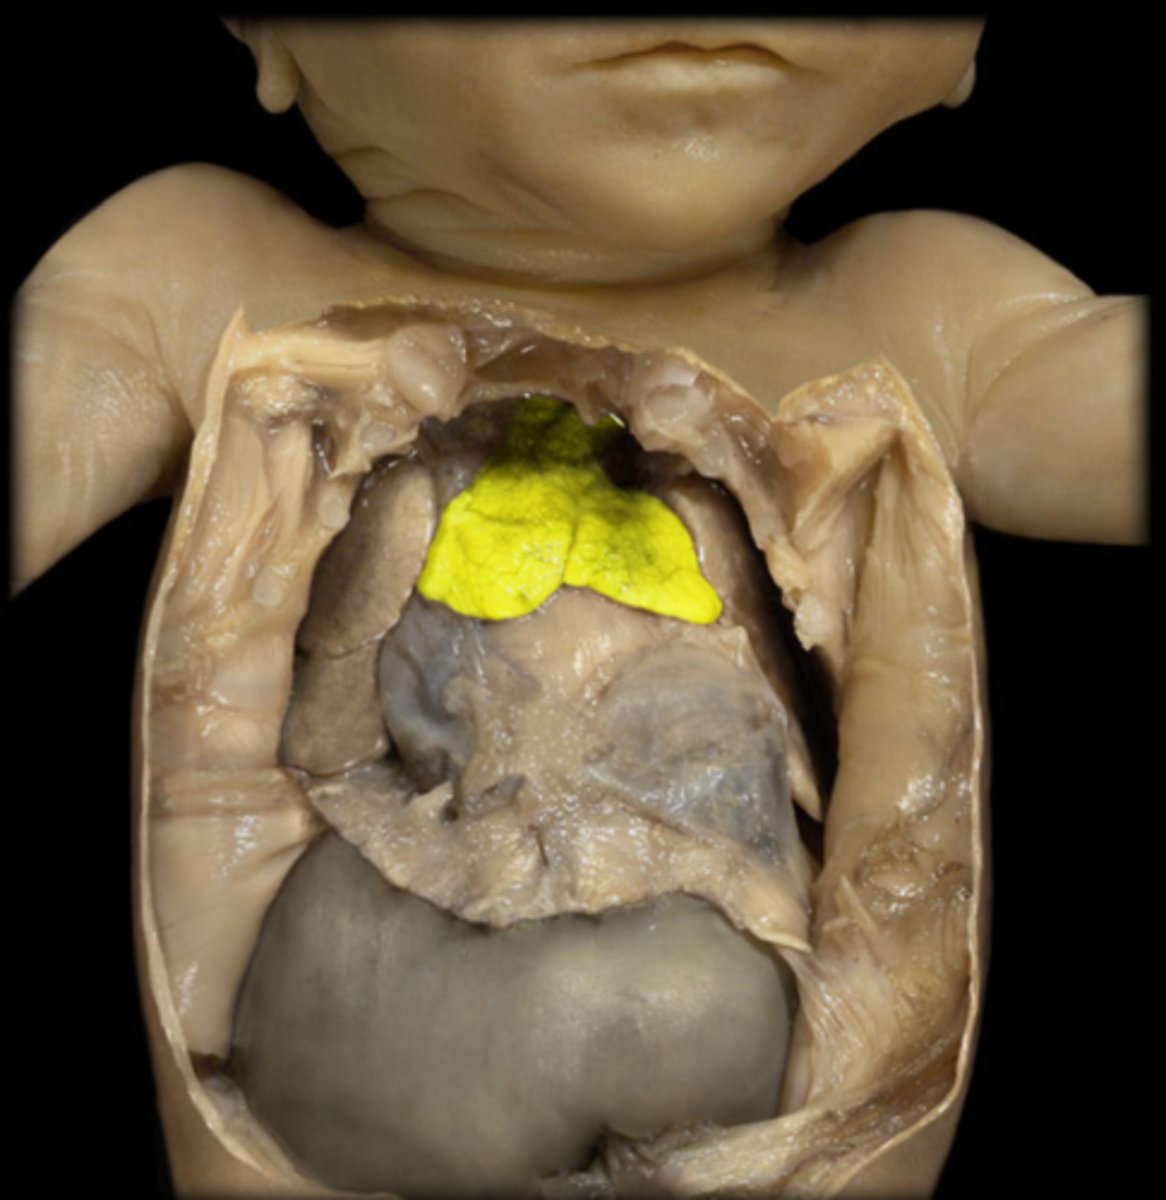

thymus

Fetal thymus

remnant of thymus

Mostly adipose tissue in adults.